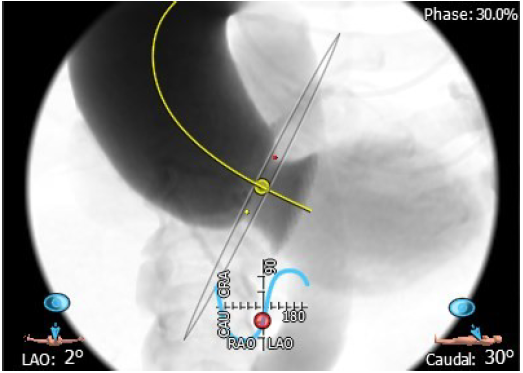

4. 患者术中造影角度LAO:2°,CAU:30°;

术中造影角度:LAO:2°,CAU:30°